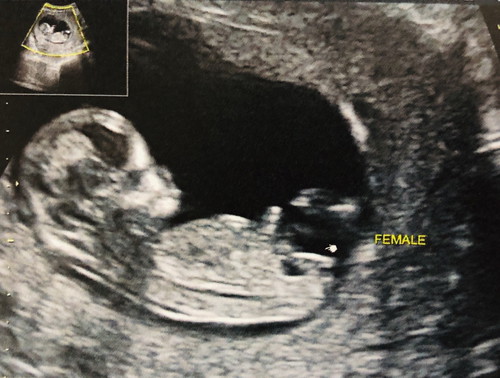

ช่วยดูหน่อยค่ะ ผู้หญิงไหม หมอบอกน่าจะผู้หญิง คนที่สองคุณแม่ดูไม่ออก @.@ ที่บ้านลุ้นอยากได้หลาน ผู้ชาย รูปซาวน์ดตอน 12w 4d ค่ะ